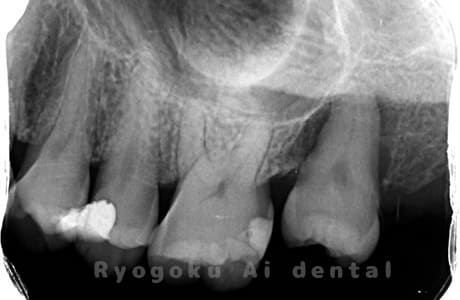

Case01

-

- 原因

- 慢性根尖性歯周炎

- 治療期間

- 3ヶ月

- 治療内容

- 自家歯牙移植手術+マイクロエンド+ダイレクトボンディング

- 治療費用

- ¥220,000

他院で根尖病変が大きく、抜歯と判断され、インプラント手術を提案された患者様です。親知らずが残存していたため、自家歯牙移植手術を行いました。

<リスク・副作用>

治療後、痛みや違和感、出血、腫れなどが出る事があります。喫煙者、糖尿病などの方の場合、歯が生着しない場合があります。